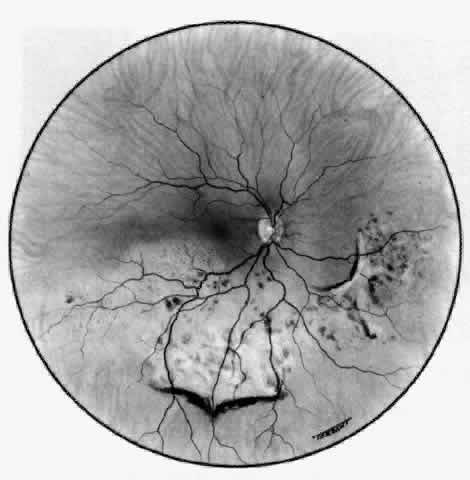

Because the posterior sclera is invisible, the diagnosis of posterior scleritis is made only if the anterior sclera is also involved or some other sign or symptom leads one to suspect it. Posterior scleritis is much more common than previously suspected, as recent clinical and pathologic studies have shown.19,28,29 There are two distinct forms of posterior scleritis. The first is usually associated with an anterior scleritis. This granulomatous disorder, like its anterior counterpart, can be diffuse, nodular, or necrotizing in character and is associated with the connective tissue diseases. The second form occurs in young patients of all races who are 9 to 40 years of age. It is always diffuse in character but is not associated with any systemic disorder. Both forms may cause uveitis if the inflammation affects the ciliary body, and in both forms the patient may develop exudative retinal detachments, choroidal folds, and swelling of the disc (Figs. 51 and 52). The granulomatous type may also involve the structures outside the globe, causing proptosis (Fig. 53), limitation of ocular muscle movement, and, uniquely, retraction of the lower lid on attempted elevation of the eye (Fig. 54). Diagnosis is with B-scan ultrasonography.

Fig. 52. Fundus appearance after resolution of exudative detachment in patient with severe posterior scleritis. Macula was affected and vision much impaired. (Watson PG: Management of scleritis. In: Recent Advances in Ophthalmology, Vol 5. London, Churchill-Livingstone, 1975)

TREATMENT